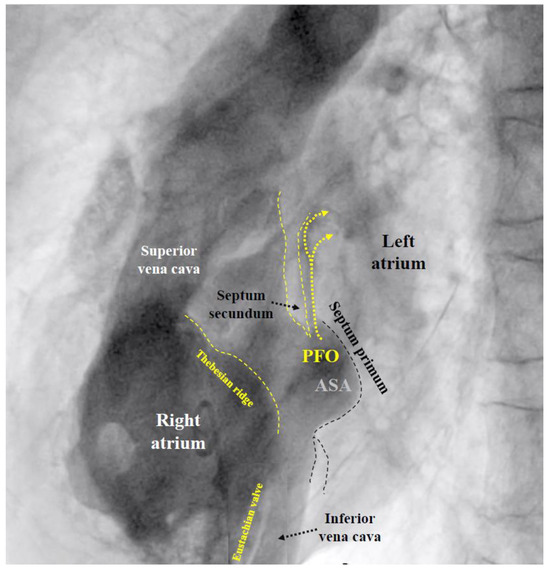

If the PFO cannot be passed despite changing the direction and position of the multipurpose catheter, the U-tip wire may be removed and the tip straightened by scratching the back of the curve with the thumb nail. Should the now straight wire still not pass, the PFO is searched for with the tip of the multipurpose catheter. If even that fails, a right atriogram with contrast medium is performed to understand the anatomy (Figure 1).

Figure 1.

Fluoroscopic contrast imaging of a patent foramen ovale (PFO) (left anterior oblique view). All important features are visible, including the Eustachian valve and the Thebesian ridge, a ledge in the free wall of the right atrium, confoundable with the atrial septum. ASA = atrial septal aneurysm.

MI: MI by paradoxical embolism through a PFO must be one of the most frequently misdiagnosed problems in cardiology [55]. This is particularly vexing because it is easily preventable by PFO closure. The cardiologists are the ones to blame for this oversight. In the wake of the bad example of neurologists, who, for nebulous reasons, want to have excluded all other putative causes for stroke before scouting for a PFO, cardiologists think of all imaginable causes of an MI before considering paradoxical embolism. In the absence of obvious atherosclerosis (the prime suspect), spontaneous coronary dissection, protracted spasm, or drug abuse are pondered, searched for, or incriminated right off the bat, but not a PFO. The mentioned fact goes ignored that atherosclerosis, age, and systemic disorders promote rather than exclude paradoxical embolism of a venous clot. Only a minority of interventional cardiologists list a PFO among the acknowledged causes of MI. The amount of blood supply to the coronary arteries is about 220 mL/minute at rest. This corresponds to almost a third of that to the brain (roughly 750 mL/minute). Both organs are equally jeopardized by the small clots typically passing through a PFO. Limbs and visceral organs require larger clots for serious ischemic harm. In the brain and heart, there are silent embolisms thanks to unimportant areas, pre-existing tissue scars, or collateralized territories. Accounting for all that, one should attribute to a PFO roughly one MI per three cerebral events. It has not yet been taken into account that neurology significantly underdiagnoses PFO-mediated cerebral events. Typically, they are ruled out by default in patients with the highest respective risk. The number of correctly diagnosed PFO-mediated MIs should probably be at least hundredfold higher than it currently is. Any acute MI looking even remotely embolic should prompt a search for a PFO, once the coronary situation is managed. This can be accomplished with a right heart catheterization at the end of the primary coronary percutaneous intervention. Rather than directly probing the PFO with a wire or a catheter as described above, a right atrial injection is preferable (Figure 1). There is a small but concerning risk of a thrombus saddling the PFO [24], part of which just broke off and caused the acute MI. Excluding or proving and closing a PFO in that way adds a few minutes to the coronary case and is doable day or night. It does not really increase the overall risk of the procedure but can do a lot of good. It makes sense in embolic-looking MIs irrespective of whether or not they were indeed caused by the PFO. The next MI could well be, and a mechanical vaccination against paradoxical embolism is never unwarranted. By the way, screening for a PFO with a right heart catheter is less uncomfortable for the patient than with a TEE. The features of the PFO to be respected when selecting the appropriate device size (Figure 4) can be equally well depicted in such a study with contrast medium (Figure 1). A combined coronary intervention and PFO closure is in the vetted interest of patients.